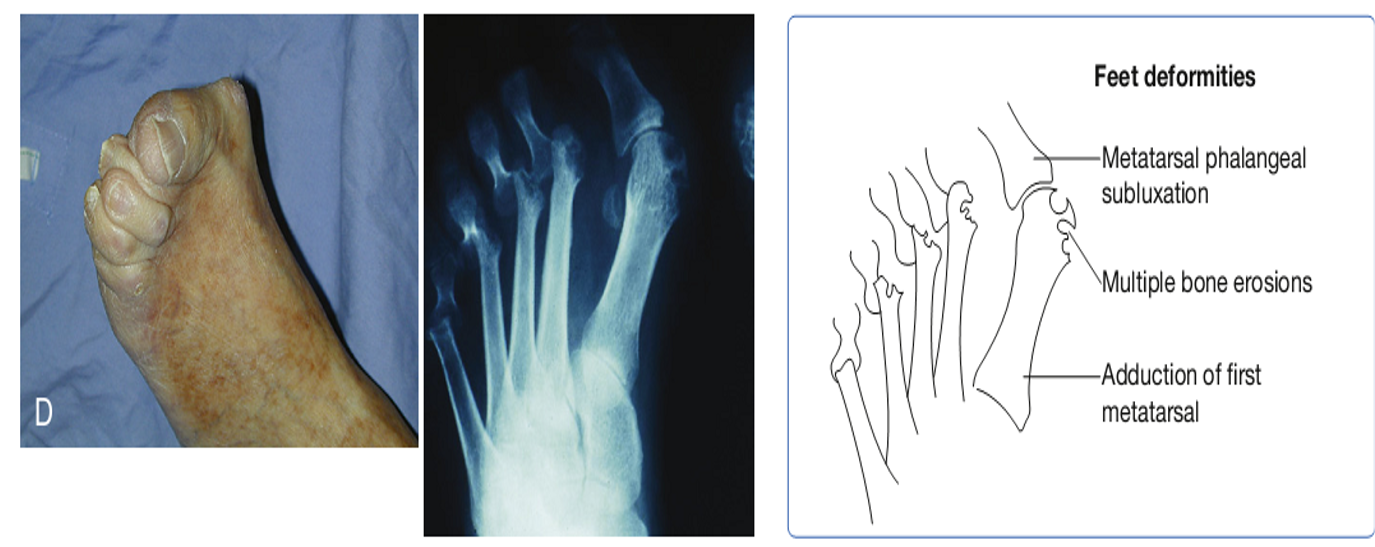

- Biến dạng khớp tiến triển: ngón tay hình thoi, cổ tay hình lưng lạc đà, bàn tay ở tư thế nửa gập và lệch trục về phía xương trụ gọi là bàn tay gió thổi, ngón tay hình cổ thiên nga, khớp gối dính ở tư thế hơi gấp.

- Giai đoạn III (tiến triển nặng) – Bằng chứng chụp X quang về sự phá hủy sụn và xương cùng với loãng xương quanh khớp; biến dạng khớp (ví dụ, bán trật, lệch trụ, quá duỗi ngón) mà không bị dính khớp; teo cơ rõ; Có thể có tổn thương mô mềm ngoài khớp (ví dụ: nốt dạng thấp, viêm bao gân)

Các biến dạng do viêm khớp dạng thấp có thể ảnh hưởng chức năng của bệnh nhân. Phần lớn các biến dạng liên quan đến bàn tay, khớp gối, bàn chân và vai. Loại dụng cụ chỉnh hình nào phụ thuộc vào khớp tổn thương và mục đích can thiệp (như phòng bàn chân rũ, giảm co rút khớp). Các dụng cụ chỉnh hình có thể làm cho người bệnh dễ dàng hơn trong các hoạt động sinh hoạt hàng ngày, đem lại mức độ độc lập lớn hơn.

Dụng cụ chỉnh hình chi dưới

Dụng cụ chỉnh hình bàn chân có thể đem lại một tiếp cận bảo tồn để giảm đau khi đi và chịu trọng lượng. Điều này có thể được thực hiện qua một số biện pháp như điều chỉnh kích thước và độ vừa của giày hoặc thay đổi vật liệu làm giày. Ngoài thay đổi giày, các dụng cụ chỉnh hình có thể được sử dụng để điều trị viêm khớp cổ, bàn chân. Dụng cụ chỉnh hình cổ bàn chân cũng có thể được sử dụng để làm giảm co rút khớp hoặc trợ giúp các cơ yếu quanh khớp. Các nẹp gối cũng rất hữu ích trong giai đoạn sưng đau.